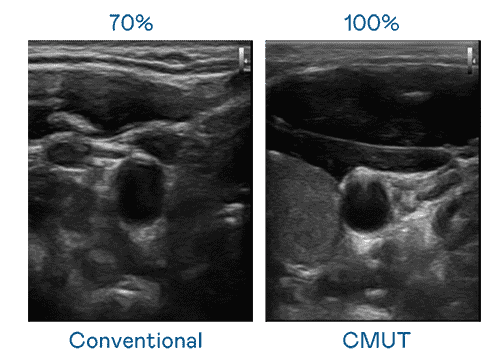

CMUT 技术是一种用电容式微机电元件来产生超音波讯号的技术。。。。与传统 PZT 压电式技术相比,,,CMUT 频宽增加 30%,,,更宽频的超音波讯号让影像解析度大幅提升,,是实现高影像品质医疗超音波扫描、、、促进精准医疗发展的关键技术。。

大频宽带来超清晰影像

超音波影像的解析度高低,,,首先取决于探头能发出的讯号频宽。。。。PA直营 CMUT 可提供高清晰的超音波讯号,,提供高频宽、、高灵敏度、、、、影像纹理细节更高的超音波影像,,,,协助医护人员缩短影像判读时间及利用精准的医疗影像进行诊断。。。